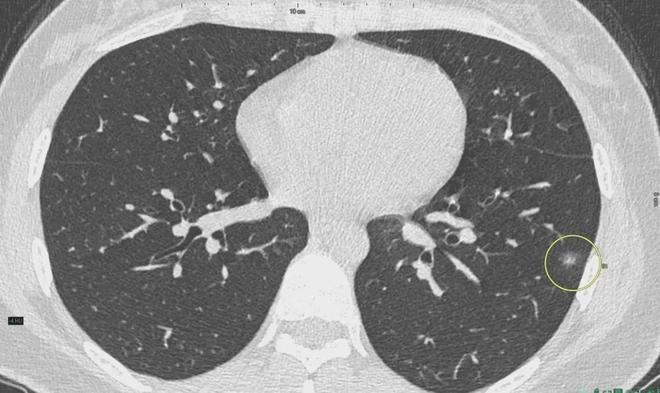

肺結(jié)節(jié)是一種常見的肺部疾病,其發(fā)病率逐年上升,雖然肺結(jié)節(jié)多數(shù)情況下是良性的,但也有可能惡化為肺癌,了解肺結(jié)節(jié)的形成原因?qū)τ陬A(yù)防和治療具有重要意義,本文將為您詳細(xì)解析肺結(jié)節(jié)的形成機(jī)制。

6、定期體檢:定期進(jìn)行肺部檢查,及時發(fā)現(xiàn)并治療肺結(jié)節(jié)。

對于已經(jīng)發(fā)現(xiàn)肺結(jié)節(jié)的患者,應(yīng)及時就醫(yī),進(jìn)行進(jìn)一步的檢查和治療,醫(yī)生會根據(jù)患者的具體情況制定個性化的治療方案,包括藥物治療、手術(shù)治療等,早期發(fā)現(xiàn)、早期治療是提高肺結(jié)節(jié)治愈率的關(guān)鍵。